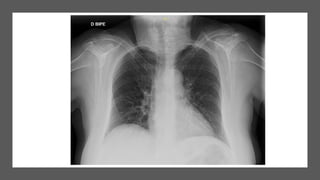

…Paciente con fiebre, cefalea y tos seca de 10 días de evolución. Aumento de reactantes de

fase aguda, patrón de citolisis, radiografía de tórax sin hallazgos significativos…